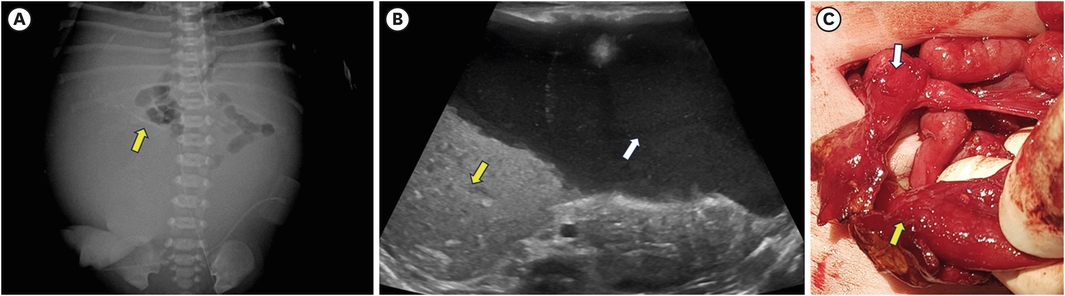

In a normally active neonate, the swallowed air usually reaches the proximal bowel within an hour and the distal small bowel within three hours [21]. In most cases, plain abdominal radiographs (supine and lateral view) demonstrate the presence of intestinal obstruction in patients. Proximal jejunal atresia may present as only a small amount of air-fluid level in the proximal dilated bowel and a gasless abdomen beyond the atresia. The more distal the atresia, the more severe the abdominal distension, with more distended bowel loops and air-fluid levels. In ileal atresia, the bowel just proximal to the atresia is much more dilated and may show more air-fluid levels, which may require differential diagnosis with meconium ileus or total colonic aganglionosis. In these cases, a contrast enema can be helpful (Fig. 5) [22]. In 12% of JIA, plain radiographs show peritoneal calcification, indicating meconium peritonitis [23]. The giant cystic meconium peritonitis is associated with late intrauterine bowel perforation, where the perforated intestine and meconium form an encapsulated mass (pseudocyst) (Fig. 6) [24]. In a survey by KAPS in 2010, meconium peritonitis was reported in 22.1% of JIA (12.5% in jejunal atresia and 31.5% in ileal atresia) [4].

Fig. 6

Meconium peritonitis. (A) Peritoneal calcifications (yellow arrow) are present in the right abdomen. This plain radiograph, taken 4 hours after birth, shows the bowel being compressed by the pseudocyst; hence, bowel gas is only visible in the proximal bowel. (B) A large amount of fluid (white arrow) with echogenic debris (yellow arrow) occupies most of the peritoneal cavity in the ultrasound. (C) The patient had a massive meconium pseudocyst that took up most of the abdominal space. After the pseudocyst was removed, a type IIIa ileal atresia (with the yellow arrow indicating the proximal end and the white arrow indicating the distal end) was confirmed. The patient recovered well post-surgery.